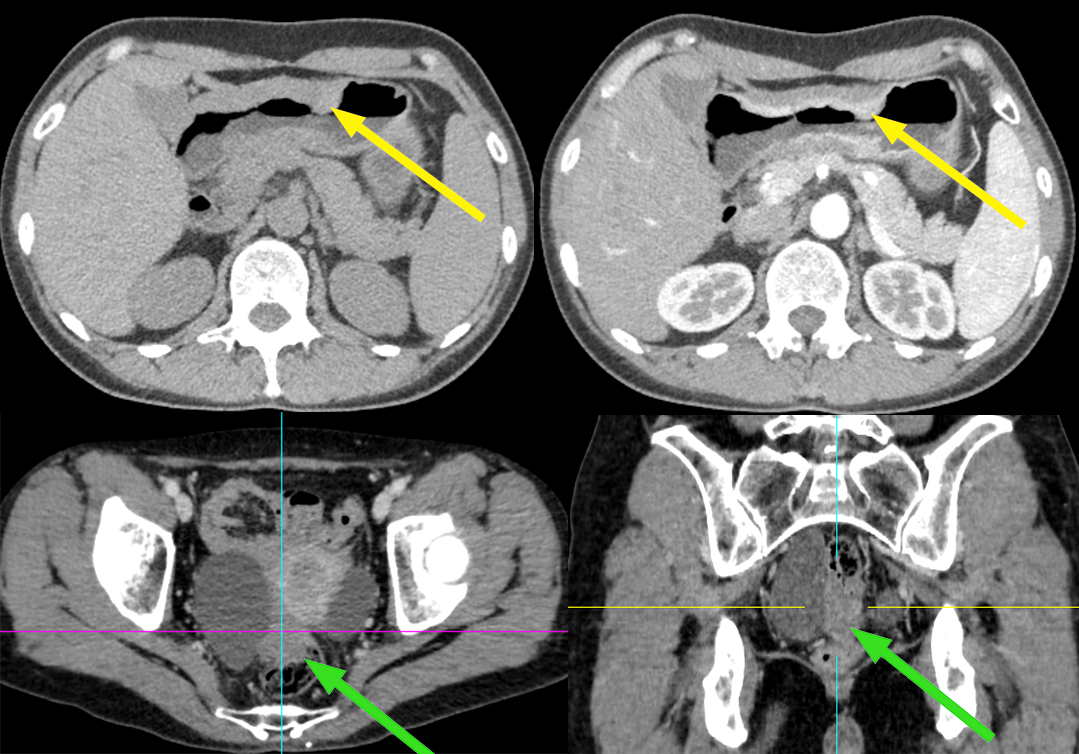

患者,女,51 岁,因上腹部不适 1 年,加重伴黑便 10 天 入院,胃镜及病理考虑胃粘液腺癌;CA125 正常。

影像描述:胃腔充盈尚可,贲门、胃小弯、胃体下部、胃角壁弥漫性增厚,不均匀明显强化,胃小弯侧浆膜层毛糙,周围脂肪间隙略浑浊,见结节样软组织影,大小约 0.8-1.0 cm,轻度强化。右侧附件区见团块状囊实混杂密度影,可见强化,与直肠分界不清。

患者,女,70 岁,因排便习惯改变 1 年入院,肠镜及病理:升结肠近回盲部中低分化腺癌;CA125 正常。

影像描述:回盲部肠壁限局性环状增厚,突向腔内,表面不光滑,管腔明显变窄,浆膜层毛糙,增强呈明显不均匀强化,与肠壁边界不清,与周围组织分界尚清,周围脂肪间隙密度增高、浑浊,可见多个结节状软组织密度影,大小约 0.4-1.3 cm,明显强化。右侧附件区见较大囊实性团块影,其内可见分隔,大小约 6.7X5.5 cm,增强扫描实性部分及分隔可见明显强化,与邻近肠管及子宫体分界略欠清。